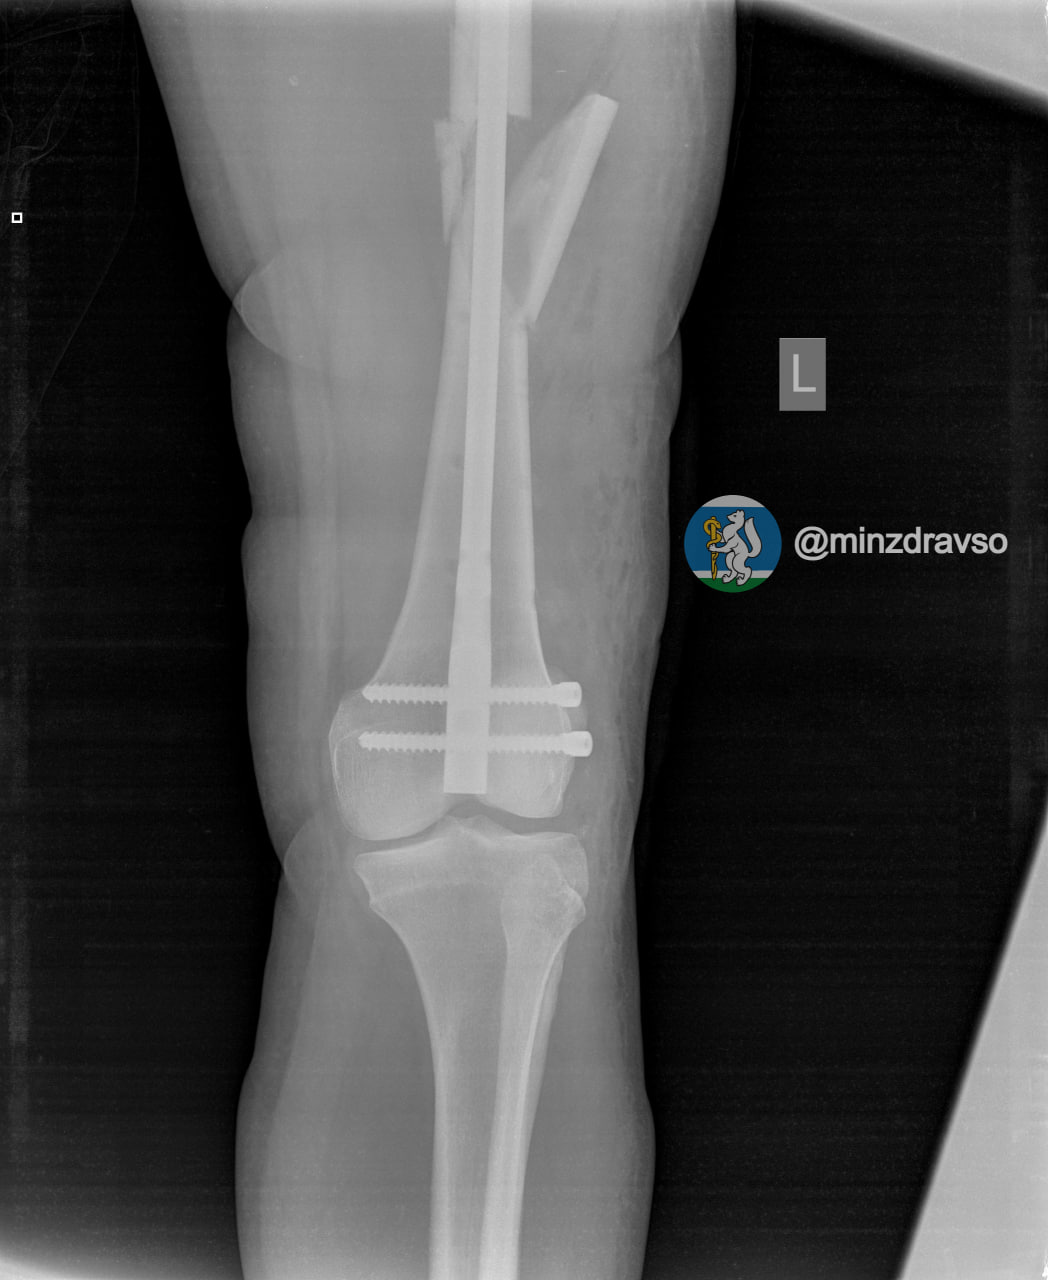

В Екатеринбурге 41-летняя беременная женщина упала с высоты десяти метров. В результате у нее диагностировали ушиб головы и сложный оскольчатый перелом левой бедренной кости, угрозы прерывания беременности медики не выявили.

Пациентке провели первую операцию в шоковой операционной приемного отделения. Через неделю, когда ее состояние стабилизировалось, женщине выполнили вторую операцию по замене аппаратов внешней фиксации на внутренний фиксатор. Для дальнейшего ведения беременности ее перевели в другую больницу.